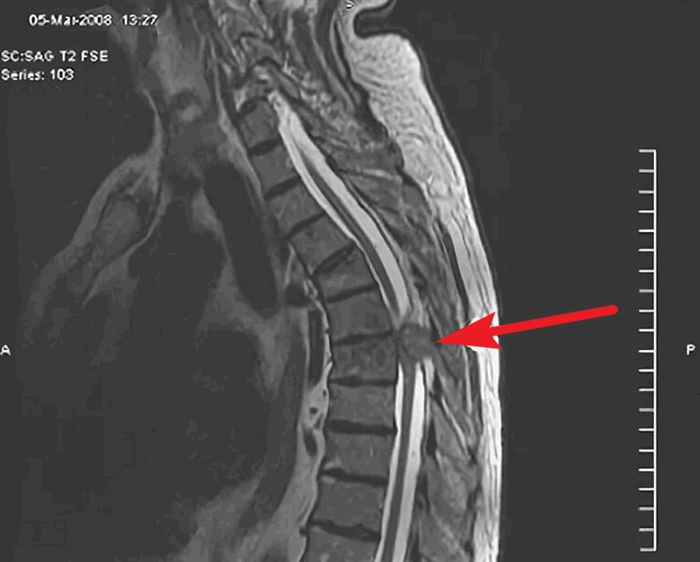

Диагноз опухоли спинного мозга ставят с помощью МРТ пораженной области спинного мозга. Альтернативой является КТ с миелографией; данный метод может помочь узнать локализацию опухоли, но предоставляет меньше информации, чем МРТ.

- Магнитно-резонансная томография. Данный метод является самым информативным в процессе диагностики. Он позволяет определить тип новообразования, его расположение и распространенность. Полученная во время обследования информация имеет высокую ценность с точки зрения планирования дальнейшего лечения. Зачастую обследование выполняют с контрастом

- МРТ позвоночника;

- Магнитно-резонансная томография. В основе метода – точная визуализация благодаря созданию магнитного поля и радиоволн. МРТ - предпочтительный метод диагностики новообразований спинного мозга и окружающих тканей. Для детального исследования конкретной области и структур возможно введение контрастных веществ.

Для окончательного диагноза опухолей спинного мозга решающее значение имеет проведение МРТ.